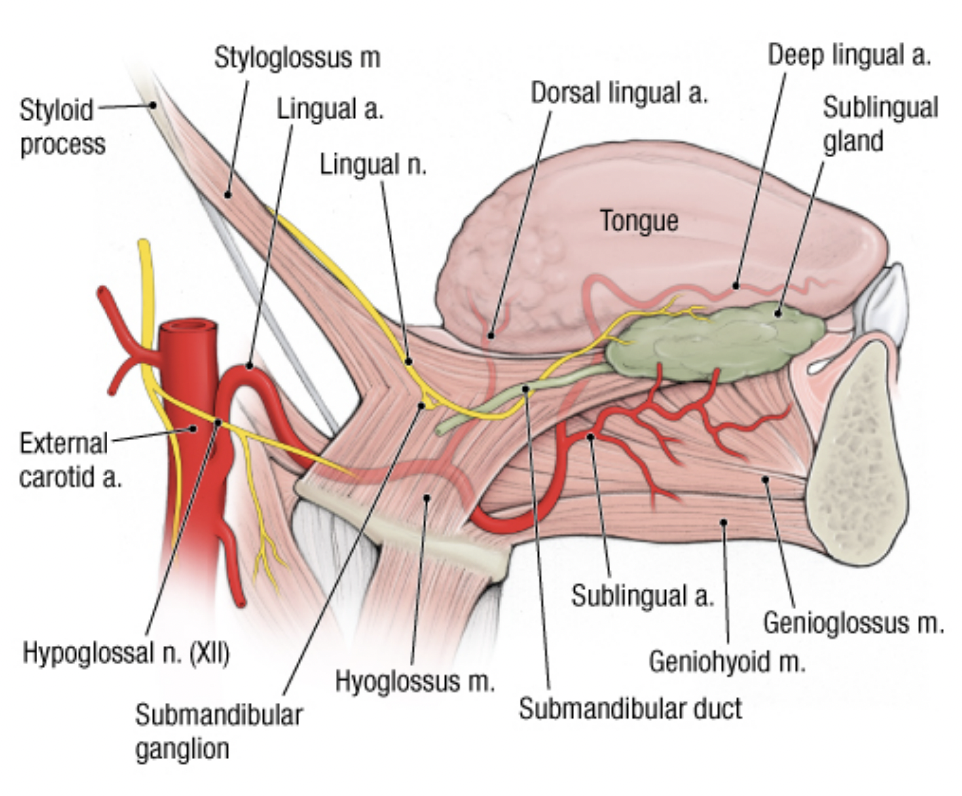

- lingual a.

- hyoglossus m. 深層,digastric下

由深而淺

lingual a. hyoglossus m. lingual v.&n.

Hyoglossus m. 外側

- Lingual n.

- Hypoglossal n.

- Submandibular duct

Lingual a.

Genioglossus m., Hyoglossus m.之間

- Deep lingual a.

- Sublingual a.

- 會合 Submental a. (Facial a. 分支)